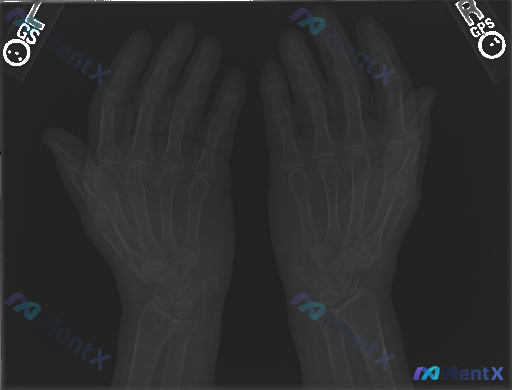

整理到一组双侧手部正位X光片的影像资料及临床背景: 影像表现 - 双侧指骨、掌骨、腕骨骨皮质连续,未见明确透亮骨折线; - 骨小梁结构尚可见,无明显局限性稀疏或异常致密增高,无明显骨质破坏或肿瘤征象; - 各掌指、指间关节对位正常,关节间隙基本对称,无明显狭窄或增宽; - 软组织轮廓清晰,未见明显肿...

整理到一组影像与临床结合的资料,想和大家讨论下这种情况的思路: 基本情况: - 影像学检查:双侧手部正位X光 - 影像所见:骨骼结构完整,骨皮质连续,未见明确骨折线、脱位;各关节间隙尚可,未见明显狭窄或破坏;骨密度、骨端形态大致正常;软组织影未见明确肿胀、钙化或占位。 - 影像初步总结:双侧手部正位...